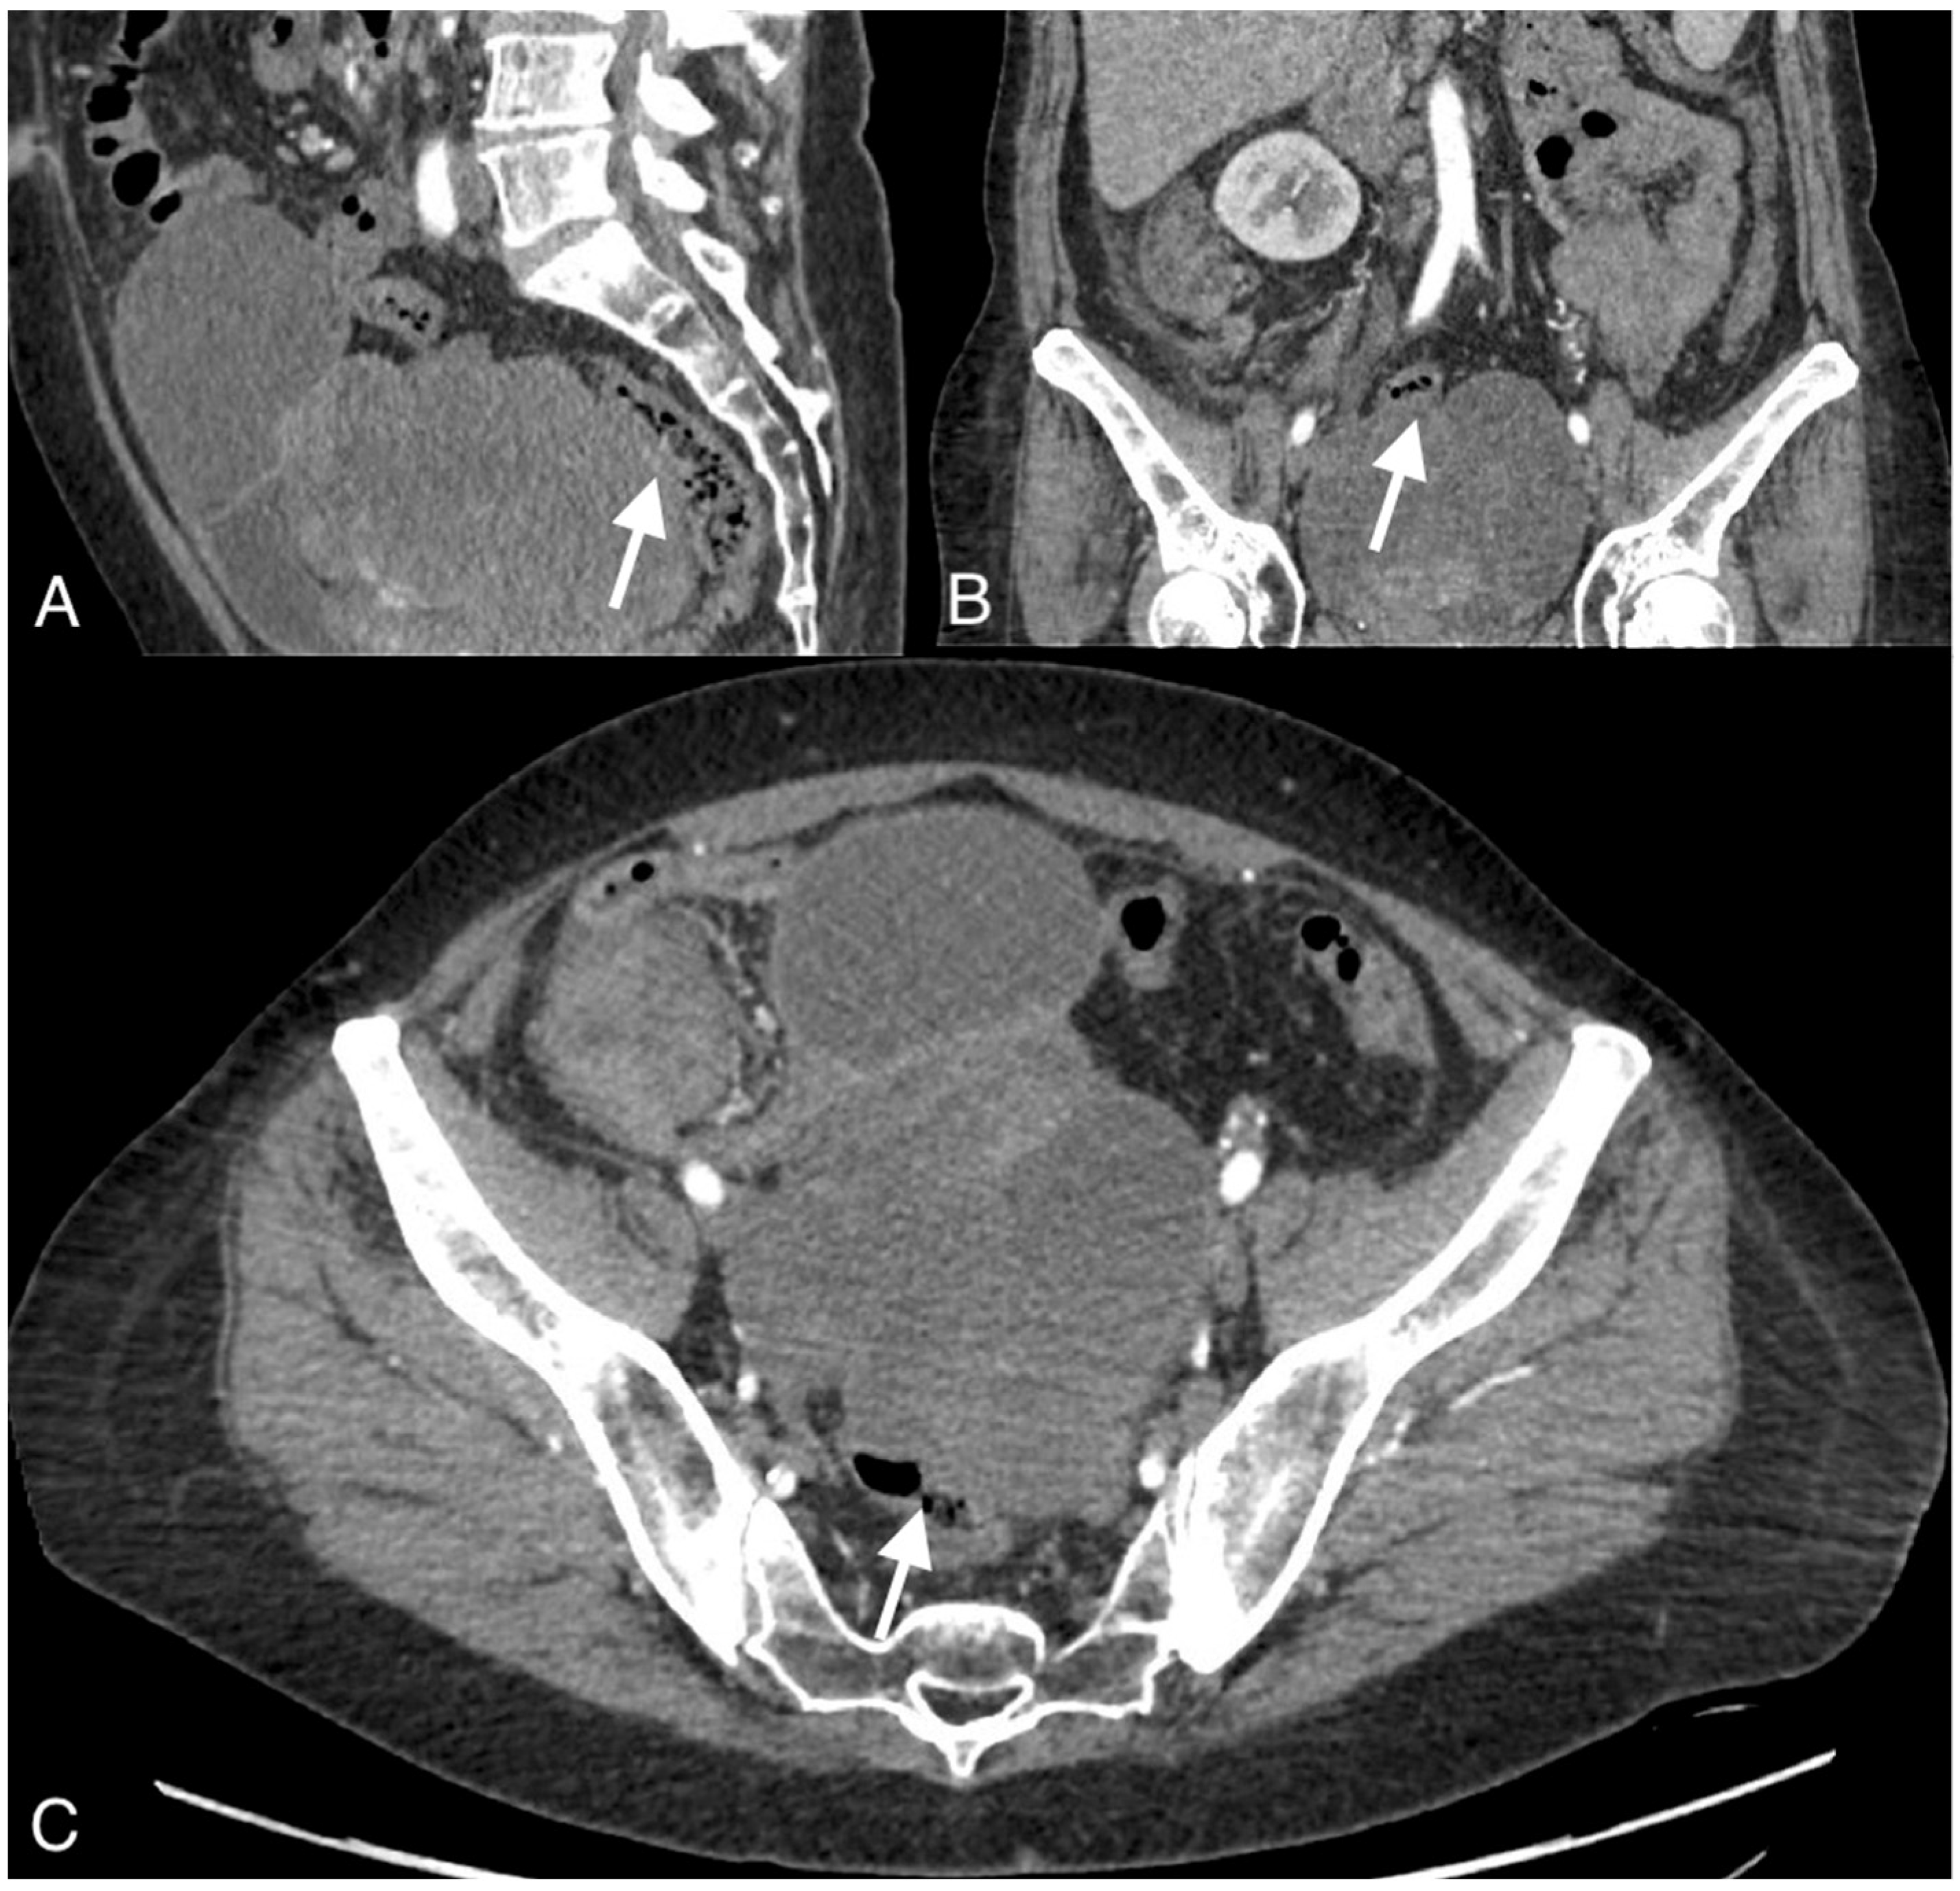

Figure 2.

Images of a 54-year-old patient with an ovarian cancer recurrence in the form of the fistula between the tumor and rectum. CT obtained in the coronal (A), sagittal (B), and axial plane (C) shows large pelvic tumor with adjacent rectum.

The median diameter of the relapsed tumor was 89 mm (range 36–130 mm). In all cases, fistulas formed between the tumor and large bowel. In three cases, fistulas formed between the rectum, including two between the sigmoid colon, one sigmoid and descending colon, one between the cecum and ascending colon, and one between the sigmoid colon and left ureter. On CT, in all cases, the fistulas were not directly visible, with only indirect signs of the fistula observed, such as infiltration of the intestine by the tumor, which we observed as vanishing of the fatty tissue between the tumor and the description of the intestinal wall, disruption of the intestinal wall, or the presence of gas in the tumor. In five patients, we observed thickening of the intestinal wall associated with a fistula (Figure 1, Figure 2 and Figure 3).

On computed tomography, we observed only indirect imaging signs of fistulas, such as infiltration of the intestine by the tumor, which we observed as vanishing of the fatty tissue between the tumor and the intestine, disruption of the intestinal wall, and gas in the tumor. Computed tomography’s limitation is evident when evaluating local tumor spread due to its lower soft tissue resolution. In other studies, CT was very useful for diagnosis, revealing indirect signs of fistulas, such as obvious thickening of the tumor wall and an air-fluid level within the tumor, suggesting that the ovarian tumor might have communication with the digestive tract; however, they also did not observe fistulas directly [11].